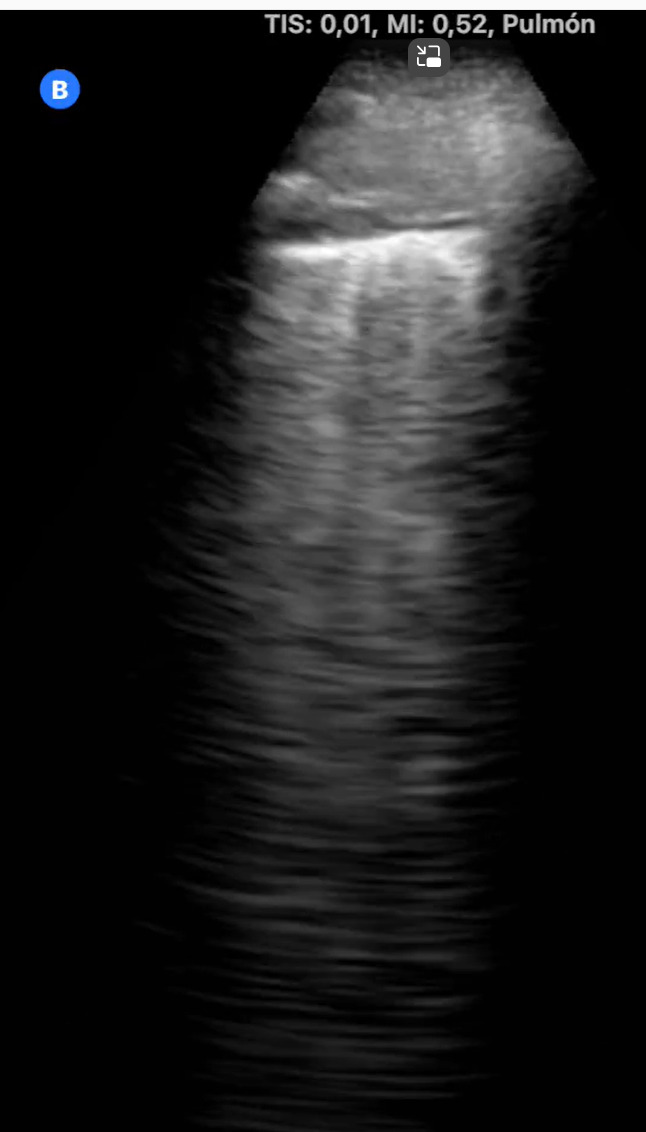

La ecografía pulmonar nos permite aumentar la capacidad diagnóstica y resolutiva, con gran rapidez y gran número de situaciones clínicas, disminuyendo el nivel de incertidumbre. Nos ayuda a tomar decisiones y ofrecer un mejor cuidado a los pacientes. Permite evaluar la extensión y gravedad de la enfermedad, así como monitorizar la progresión y evaluar las complicaciones.

Además, ayudándonos de la ecografía pulmonar, hemos podido diagnosticar diferentes patologías pulmonares intersticiales como neumonitis intersticial por metotrexate, neumopatía intersticial tipo NINE y síndrome alveolo intersticial.

La ecografía es una herramienta valiosa en la evaluación y manejo de patologías pulmonares intersticiales, proporcionando información clave que puede influir en el tratamiento y pronóstico del paciente.

Nos permite realizar un diagnóstico diferencial, evaluar derrames pleurales, monitorizar enfermedades, guiar procedimientos, diagnosticar neumonías o infecciones, valorar la función pulmonar proporcionando información sobre la estructura pulmonar que puede correlacionarse con la función respiratoria.